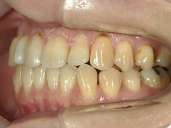

矯正歯科 治療前 右

矯正歯科 治療後 右